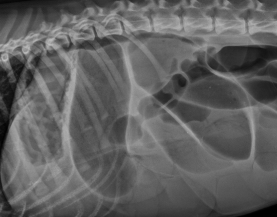

Megaesophagus

Et: Congenital, Idiopathic (#1 dogs), MG, Hiatal hernia, Reflux esophagitis

R/O: Esophageal Obstruction → cause diffusely dilated esophagus

Cs: Regurg after weaning, Diffuse dilation, weight loss

Dt: lab work, Rads, barium esophagram, AchR antibody (MG 25%)**, cortisol, lead, thyroid

Tx: upright feeding (Bailey chair), small soft meals, G tube feeding, pyridostigmine (MG), immunosuppressives (MG)